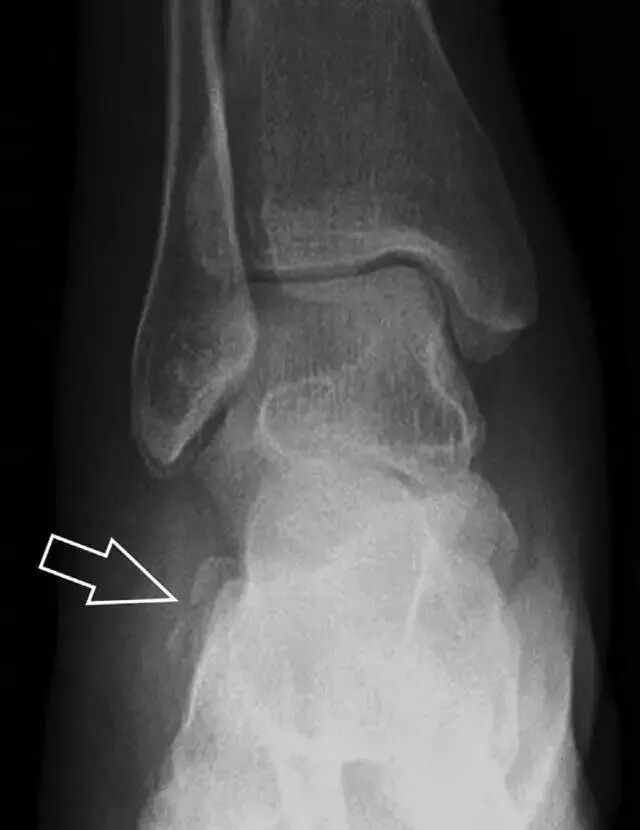

涉及到三角韧带和外侧副韧带(LCL)的复杂性骨折常常不难发现,尤其是存在表面软组织肿胀时。然而,后胫腓韧带牵拉引起的胫骨后踝骨折则很难发现。这些骨折大小不一(图 2),却很重要,因为他们常与胫骨远端螺旋骨折有关,或者是三踝骨折的一部分。

图 2 胫骨后踝骨折。A 侧位片示来源于胫骨后踝的一个小骨折碎片(箭头),因踝部扭伤导致;B 另一位跖屈损伤的患者,侧位片示一个大骨折块(箭头)